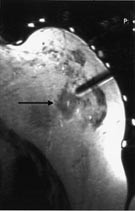

Tumordiagnostikk hos pasienter som har silikonimplantater som ledd i en brystrekonstruksjon eller av kosmetiske grunner, er vanskelig med mammografi. Dersom heller ikke ultralydundersøkelse, eventuelt med ultralydveiledet aspirasjonscytologi, gir avklaring, kan det hos denne pasientgruppen være indikasjon for MR-undersøkelse ved tumormistanke. Ved vevsprøvetaking fra tumorsuspekte områder nær implantatet kan det være en risiko for å punktere silikonprotesen. Våre egne erfaringer viser at MR-veiledet biopsi eller finnålsaspirasjon av tumorsuspekte områder er et alternativ i slike tilfeller (fig 3).